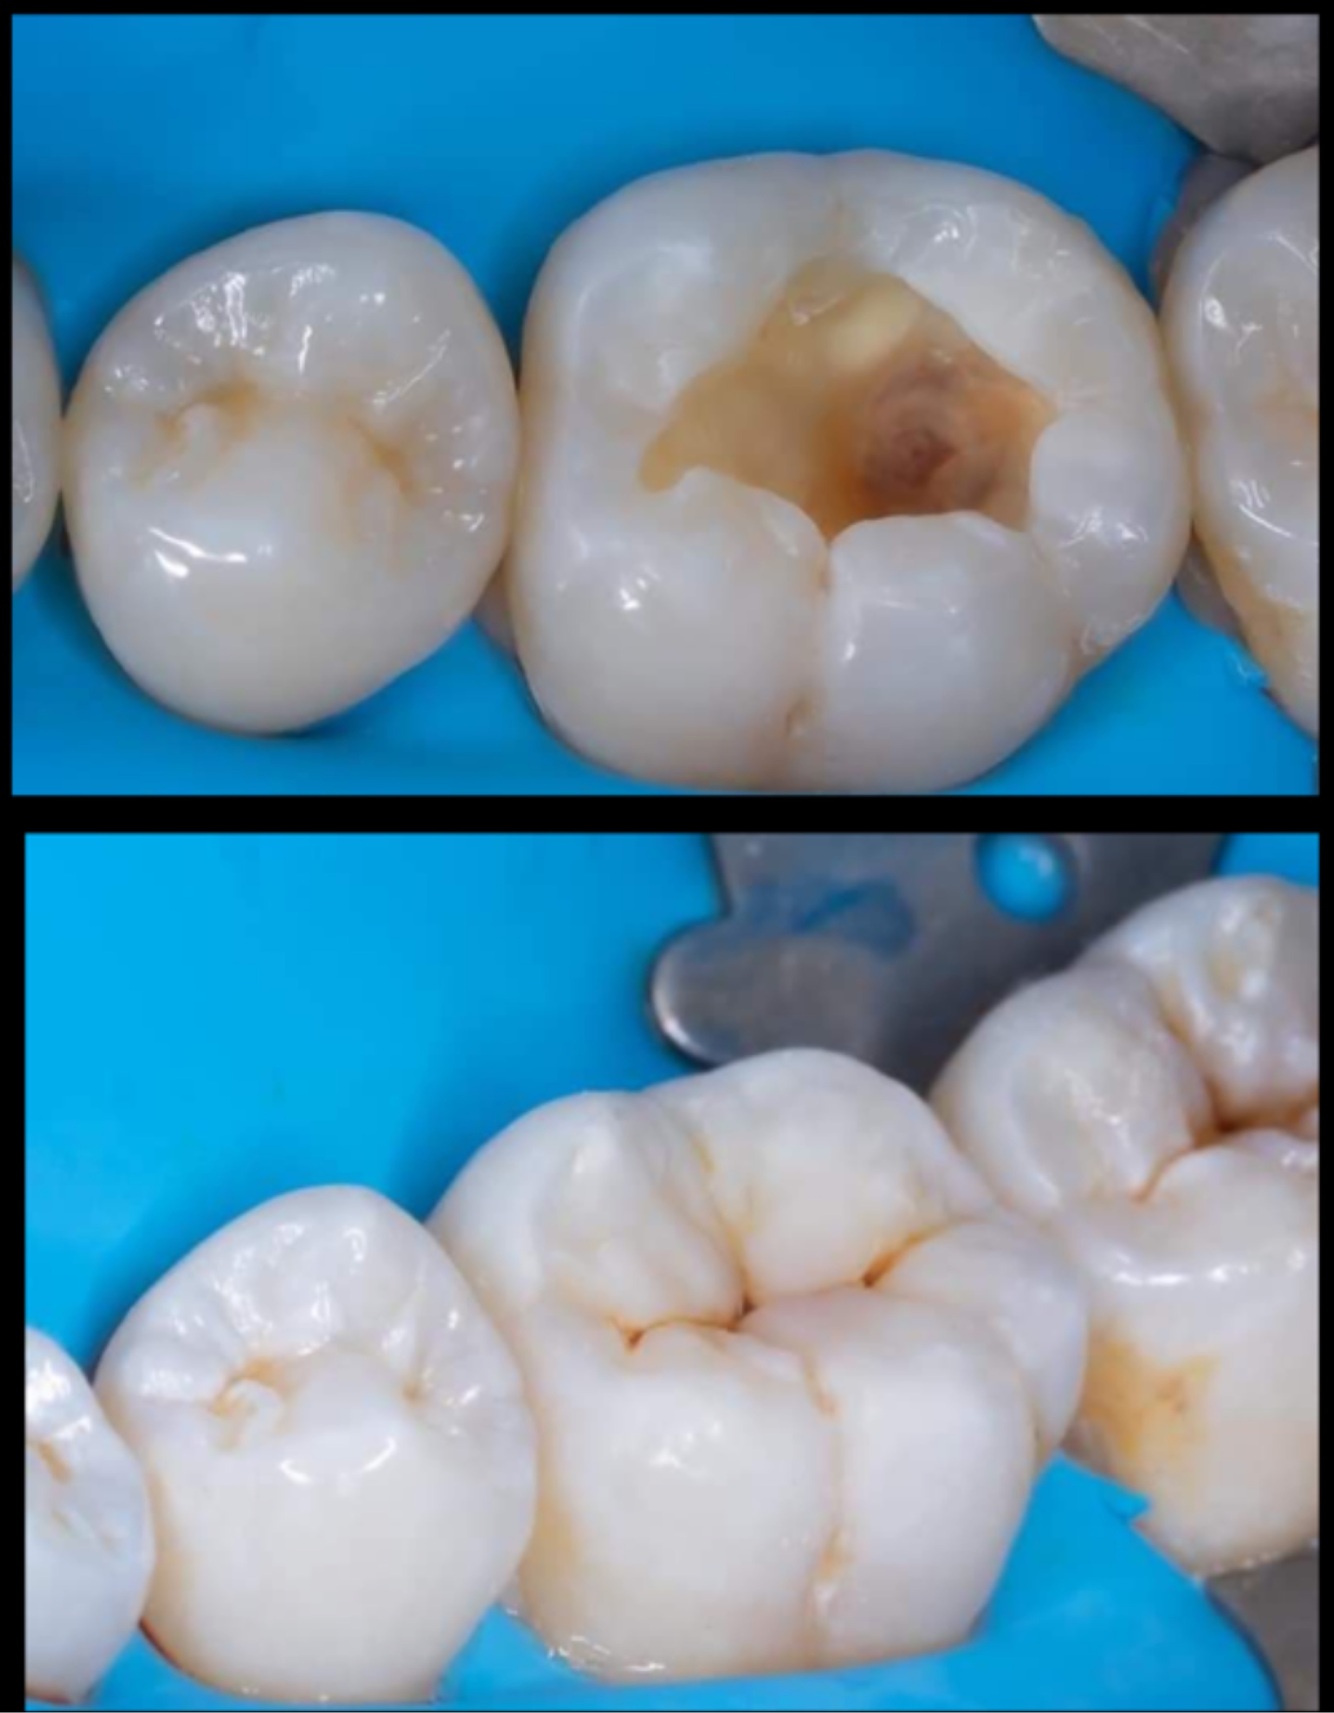

Q

The RCT done on:

Upper premolar

Upper molar

Lower premolar

Lower molar

A